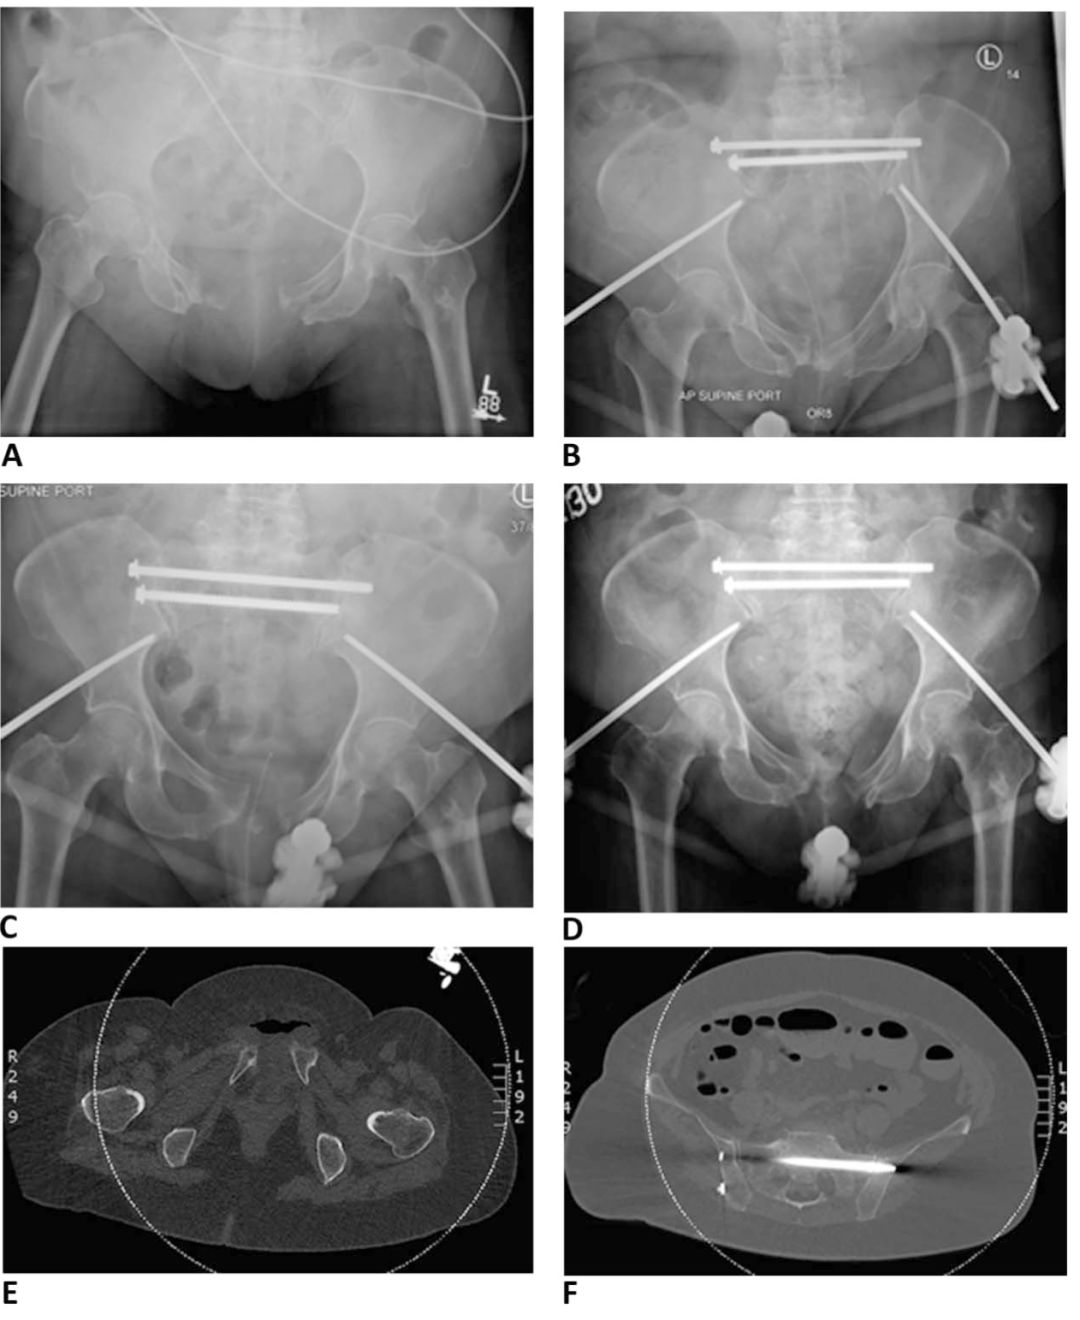

骨盆前环外固定术后最常见的并发症是钉道感染,发生率高达18%-50%。通常需要松解周围皮肤和反复换药处理。如果进展为蜂窝织炎或持续有渗出时需要抗生素治疗。持续感染会导致螺钉松动,根据感染情况,选择移除或更换螺钉固定。外固定架还可能会导致复位丢失(见图2)。外固定架治疗不稳定型骨盆前环损伤可能会导致畸形愈合。Dickson等研究报道了“外固定架畸形”的存在,并将其定义为:后环完全断裂的情况下,前方外固定架会引起屈曲、内旋畸形。

图2所示。A.68岁女性,车祸导致骨盆环前后挤压损伤(APC-II型),同时合并膀胱破裂。B.髋臼外固定架和S1/S2骶髂螺钉固定。C.术后1周显示前环复位丢失。D.术后6周,尽管后环复位,但前环逐渐复位消失。E.CT显示前环分离复位丢失。F.CT显示后环复位良好。